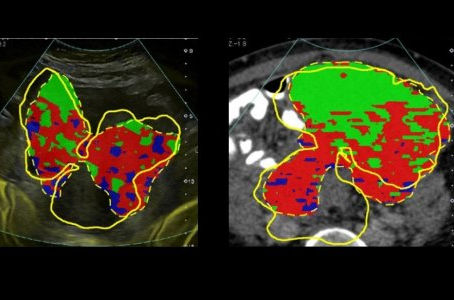

University of Cambridge Scientists' Virtual Biopsies could replace tissue biopsies in future.

A new advanced computing technique using routine medical scans to enable doctors to take fewer, more accurate tumour biopsies, has been...